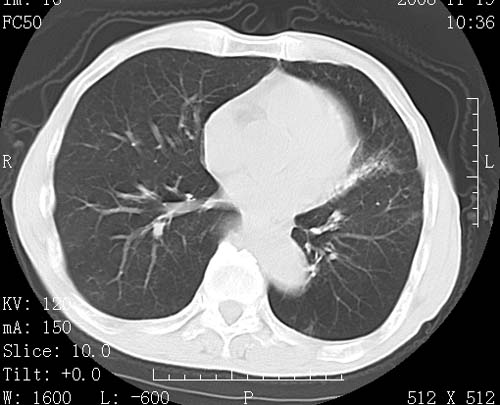

标题: CT16691:m 67 胃镜确诊食管下段及贲门癌 [打印本页]

标题: CT16691:m 67 胃镜确诊食管下段及贲门癌

术前查体,双肺部结节是转移?结核?请点评

1)符合食管癌表现。2)两肺及纵隔淋巴结多发性转移瘤。3)左肺上叶舌段及两肺下叶炎症感染。

食管癌伴双肺转移,评述:肺部毛细血管网丰富,全身血液均快速流经肺部,癌细胞容易过滤定植,形成转移瘤,影象特点为以毛细血管末梢为中心的结节灶,边缘光滑锐利,少见有中心空洞着,不同来源的转移瘤可有各自特点,如甲状腺癌为双肺弥漫性微结节,本例有原发灶,双肺影象灶典型,左肺舌段条带状网格样伴胸膜天幕征,可视为癌性淋巴管炎。